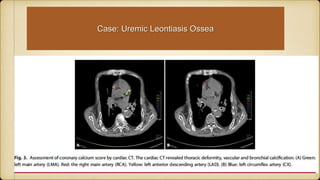

Case: Uremic Leontiasis Ossea